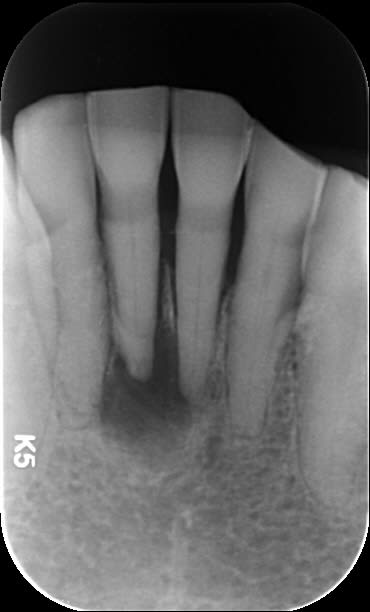

Je soigne une patiente de 88 ans, plutôt en bonne santé qui présentait une infection apicale sur 31 il y a 1 an. Voussure vestibulaire, pas vraiment douloureuse.

Les dents sont peu mobiles, pas douloureuses, légère voussure vestibulaire. Du coup la patiente est réticente pour l'extraction mais je pense qu'on le fera quand même.

Le ttt endo était déjà sport. Il y a une pap sur laquelle je peux faire une brasure mais c'est surtout 31 et 42 qui m'emmerde, je pense que 41 c'est plié

A la base je pense qu'il y avait un second canal en lingual. Regarde les coupes horizontales tu devrais le trouver ou au moins l'imaginer. Sur les coupes sagittales, le canal que tu as obture est deporte en vestibulaire, c'est une bonne indication. Sur la retro tu vois bien les deux racines de l'incisive latérale, tu trouves en general 2 canaux sur la centrale dans ce cas la.

Visiblement les images aux apex des dents adjacentes ne gène personne. Je vais tenter de trouver la racine linguale, de mémoire c'était bien calcifié. Je verrai bien et on risque pas grand chose de toute façon